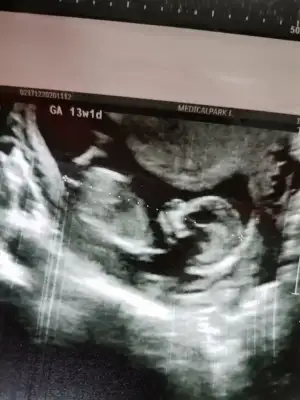

Canım 16. Haftadan önce kesin söylüyolarmı cinsiyeti? Bende 16. Haftayı bekliyorum öğrenmek içinBu gün tam 13+1 günlük olduk geçen hafta doktor kız gibi dedi emin değilim dedi ama bu gün kız dedi

Kız gibi emin olamadım başka USG varsa paylaşın 11 12 13 haftalar olmalı

Şimdilik erkek yönünde en iyi nub için 11 12 13 haftalar olmalı tekrar paylaşın

Banada bakarmısınız bu gün doktor kız dedi yüzde doksan dediEn iyi 11 12 13 haftalar olmalı

Kız görünüyorBanada bakarmısınız bu gün doktor kız dedi yüzde doksan dedi